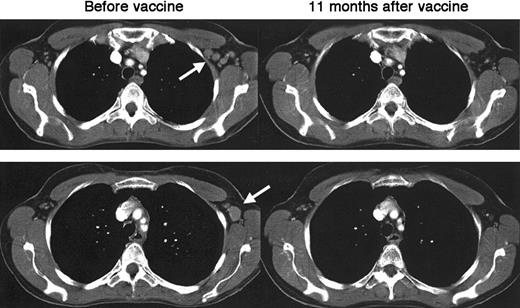

Evidence of antitumor activity was seen in 4 of the 10 patients, including 2 who experienced CR. Complete regression of paracardiac and mediastinal lymph nodes occurred in patient D1.22 This patient's remission lasted 44 months, after which recurrent disease was confined almost exclusively to bone, while all known prior sites of disease were spared. Patient D9 experienced complete regression of axillary (Figure 1), peri-aortic, and iliac lymph nodes. This patient's CR lasted 57 months, when recurrent disease was detected in a single previously uninvolved site (left thyroid). Patient D2 had a PR of peri-aortic and para-iliac nodes lasting 12 months. In patient D3, the only evidence of disease at the time of vaccination was a tumor-specific PCR signal in the bone marrow that became negative after vaccination,22 and she has remained without clinical evidence of disease progression for more than 6 years. Of the 4 patients with clinical responses, 3 of 4 had T-cell anti-Id immune responses, and patient D9 had no detectable in vitro anti-Id response despite having achieved durable CR. There was no correlation of immune or clinical responses to the number of DCs infused. Follow-up status of the 10 patients is listed in Table 1. All 10 patients remain alive at a median follow-up of 64 months after vaccination (range, 47-94 months) and 103 months after diagnosis (range, 81-276 months). Patient D3 has not received any subsequent treatments, and the remaining patients have undergone additional treatments as indicated. Patient D8 remains in CR after booster vaccinations with Id-KLH protein (see below and Table 3).

Complete regression of lymphoma after idiotype-pulsed dendritic cell vaccination.

CT images of the chest of patient D9 show multiple enlarged left axillary lymph nodes that normalized 11 months after vaccination. Arrows indicate sites of disease before vaccination. Similarly sized lymph nodes in the periaortic and iliac regions also completely regressed.